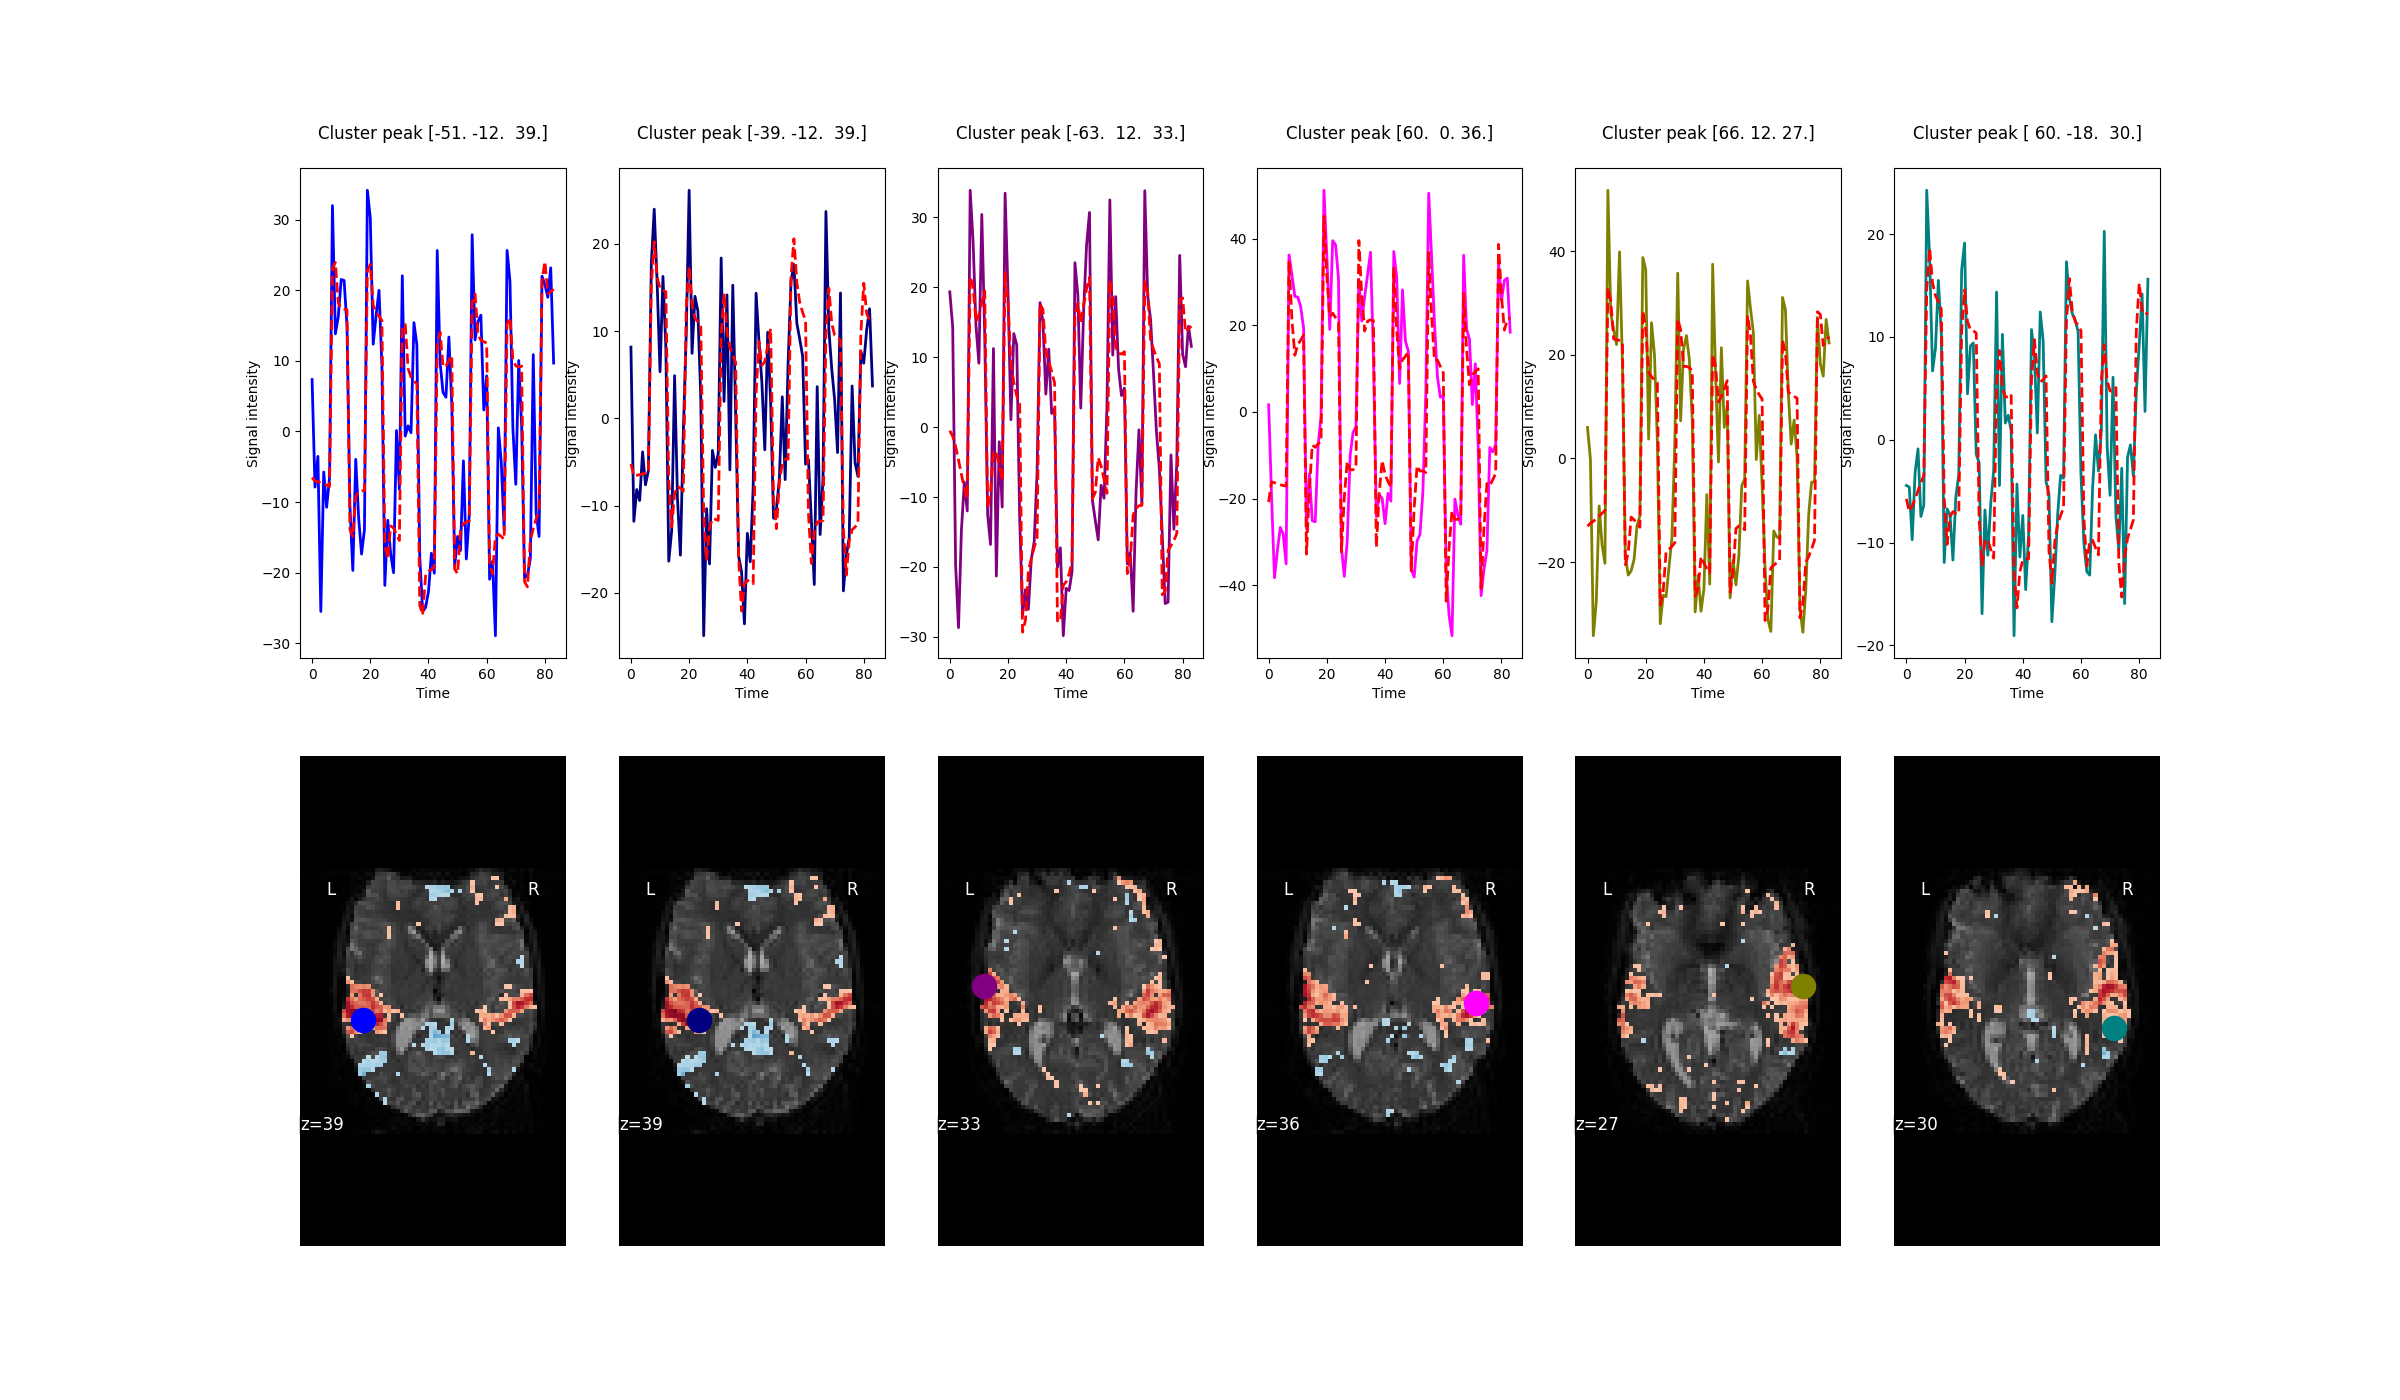

One way to assess the quality of the fit is to compare the observed and predicted time series of voxels.

Nilearn makes the predicted time series easily accessible via a parameter called predicted that is part

of the nilearn.glm.first_level.FirstLevelModel. This parameter is populated when

FistLevelModel is initialized with the minimize_memory flag set to False.

observed_timeseries = masker.fit_transform(fmri_img)

predicted_timeseries = masker.fit_transform(fmri_glm.predicted[0])

Here, masker is an object of nilearn.maskers.NiftiSpheresMasker. In the figure below,

predicted (red) and observed (not red) timecourses of 6 voxels are shown.

In addition to the predicted timecourses, this flag also yields the residuals of the GLM. The residuals are useful to calculate the F and R-squared statistic. For more information refer to Predicted time series and residuals